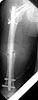

Lt femur

Attached here few x-rays of a multi-trauma patient. He is a 51years old man,sustain MVA at 08/15/99 and refer to our hospital few days ago, more than twoweeks after injury. He sustain Bilateral femoral fracture including femoralneck, A right humerus fracture, right distal radius fx, left open ulnar fx,right tibial plateau (type III) fx and Chopart fracture dislocation of the rightfoot. At the other hospital where he was admitted, He underwent laparotomy andfixation of both femur by reconstruction IMN, application of Ex Fix to thehumerus, and reduction and K.W. fixation of the Rt foot. He is currently stable and conscious. He is scheduled next week for replacing of the Rt IMN to aretrograde nail and pinning (6.5 mm screws) of the neck fracture, fixation ofthe ulna, distal radius and tibial plateau.

We are seeking for ideas about the left femur: either tore-operate or leave it as is, and if to operate - what approach.